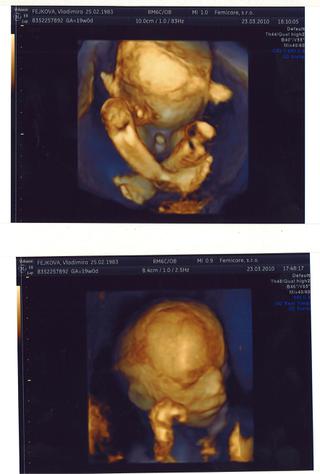

a ja konecne pridavam foto z 3D sona ako dokaz aj turecky sed s pimpasom 😀